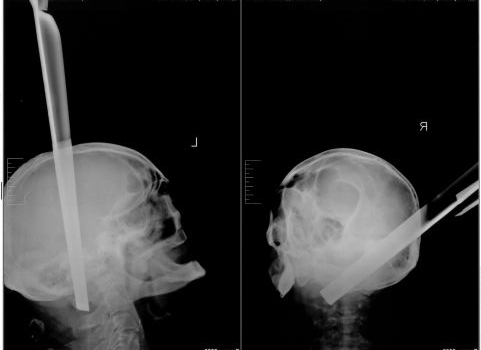

Табурет буквально торчал из головы больного - одна из ножек пробила череп в области затылка, пройдя на 11 сантиметров до самого его основания, сквозь вещество головного мозга. Пациента экстренно увезли в операционную, где дежурная бригада нейрохирургов с величайшей осторожностью извлекла инородное тело из головы мужчины.

- После удаления столь массивного предмета во время операции у больного не возникло даже ожидаемого кровотечения, - рассказывают нейрохирурги Красноярской краевой клинической больницы. - Удивительно, но факт: пациент остался жив. Мужчина провел две недели в нейрореанимации в тяжелом состоянии, где, на фоне интенсивной терапии его состояние стабилизировалось.